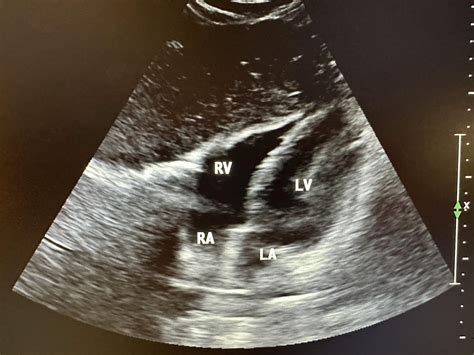

• Cardiology: Known as an echocardiogram, this uses ultrasonography to visualize the heart’s valves and chambers.